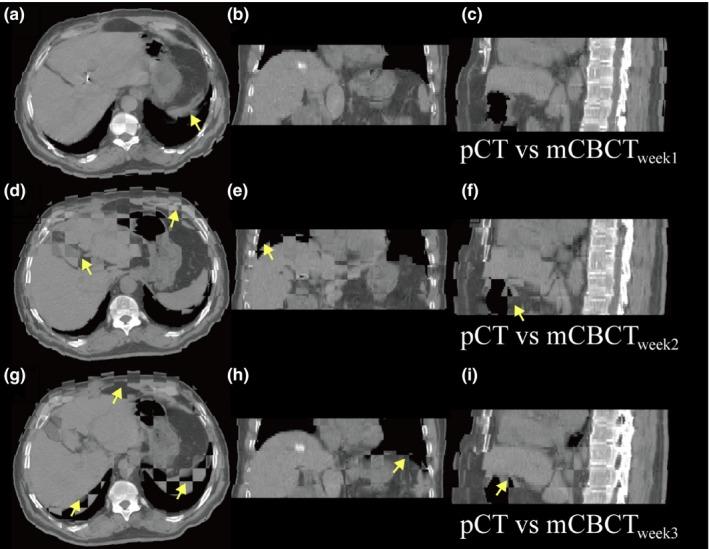

Many patients with technically unresectable or medically inoperable hepatocellular carcinoma (HCC) had hepatic anatomy variations as a result of interfraction deformation during fractionated radiotherapy. We conducted this retrospective study to investigate interfractional normal liver dosimetric consequences via reconstructing weekly dose in HCC patients. Twenty-three patients with HCC received conventional fractionated three-dimensional conformal radiation therapy (3DCRT) were enrolled in this retrospective investigation. Among them, seven patients had been diagnosed of radiation-induced liver disease (RILD) and the other 16 patients had good prognosis after treatment course. The cone-beam CT (CBCT) scans were acquired once weekly for each patient throughout the treatment, deformable image registration (DIR) of planning CT (pCT) and CBCT was performed to acquire modified CBCT (mCBCT), and the structural contours were propagated by the DIR. The same plan was applied to mCBCT to perform dose calculation. Weekly dose distribution was displayed on the pCT dose space and compared using dose difference, target coverage, and dose volume histograms. Statistical analysis was performed to identify the significant dosimetric variations. Among the 23 patients, the three weekly normal liver D increased by 0.2 Gy, 4.2 Gy, and 4.7 Gy, respectively, for patients with RILD, and 1.0 Gy, 2.7 Gy, and 3.1 Gy, respectively, for patients without RILD. Mean dose to the normal liver (D) increased by 0.5 Gy, 2.6 Gy, and 4.0 Gy, respectively, for patients with RILD, and 0.4 Gy, 3.1 Gy, and 3.4 Gy, respectively, for patients without RILD. Regarding patients with RILD, the average values of the third weekly D and D were both over hepatic radiation tolerance, while the values of patients without RILD were below. The dosimetric consequence showed that the liver dose between patients with and without RILD were different relative to the planned dose, and the RILD patients suffered from liver dose over hepatic radiation tolerance. Evaluation of routinely acquired CBCT images during radiation therapy provides biological information on the organs at risk, and dose estimation based on mCBCT could potentially form the basis for personalized response adaptive therapy.

许多技术上无法切除或医学上无法手术的肝细胞癌(HCC)患者在分次放疗期间因分次间变形而出现肝脏解剖结构变异。我们进行了这项回顾性研究,通过重建HCC患者的每周剂量来调查分次间正常肝脏的剂量学后果。23例接受常规分次三维适形放疗(3DCRT)的HCC患者纳入了这项回顾性研究。其中,7例患者被诊断为放射性肝病(RILD),另外16例患者治疗后预后良好。在整个治疗过程中,每周为每位患者进行一次锥束CT(CBCT)扫描,对计划CT(pCT)和CBCT进行可变形图像配准(DIR)以获取修正后的CBCT(mCBCT),并通过DIR传播结构轮廓。将相同的计划应用于mCBCT进行剂量计算。每周剂量分布显示在pCT剂量空间上,并使用剂量差异、靶区覆盖和剂量体积直方图进行比较。进行统计分析以确定显著的剂量学变异。在这23例患者中,有RILD的患者每周三次正常肝脏剂量分别增加0.2 Gy、4.2 Gy和4.7 Gy,无RILD的患者分别增加至1.0 Gy、2.7 Gy和3.1 Gy。有RILD的患者正常肝脏的平均剂量(D)分别增加0.5 Gy、2.6 Gy和4.0 Gy,无RILD的患者分别增加0.4 Gy、3.1 Gy和3.4 Gy。对于有RILD的患者,第三次每周D和D的平均值均超过肝脏放射耐受量,而无RILD的患者的值低于该耐受量。剂量学结果表明,有和无RILD的患者之间的肝脏剂量相对于计划剂量有所不同,且RILD患者的肝脏剂量超过肝脏放射耐受量。放疗期间对常规获取的CBCT图像进行评估可提供有关危及器官的生物学信息,基于mCBCT的剂量估计可能为个性化反应适应性治疗奠定基础。